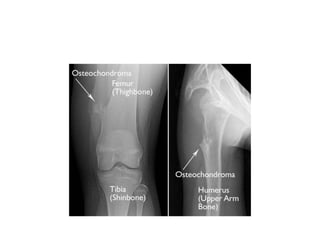

CLINICAL DESCRIPTION: Increase insize in the first decade of life Pedunculated or sessile and can vary widely in size Nearly , 15% of all patients with osteochondromas have multiple lessions Fascial bones are not affected Majority are asymptomatic and located in bones that develop from cartilage, especially the long bones of the extremities ,predominantly around the knee

Majority are asymptomatic and located in bones that develop from

cartilage, especially the long bones of the extremities ,predominantly

around the knee